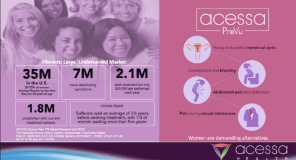

ABOUT FIBROIDS: Fibroids are benign, non-cancerous tumors in a woman’s uterus that often appear during childbearing years. Also called leiomyomas, fibroids are made up of muscle and connective tissue and may range in size from microscopic to larger than a grapefruit. The rate at which they grow is unpredictable, and a woman may have more than one fibroid at a time. While some fibroids are asymptomatic, others can be very painful and cause heavy bleeding, pressure on the bladder or rectum, a distended abdomen, and a lack of energy stemming from anemia. The majority of American women will develop fibroids at some point in their lives. According to the National Institutes of Health (NIH), at least 70 percent of women in the U.S. will develop fibroids by age 50, and the prevalence is even higher among African American women.